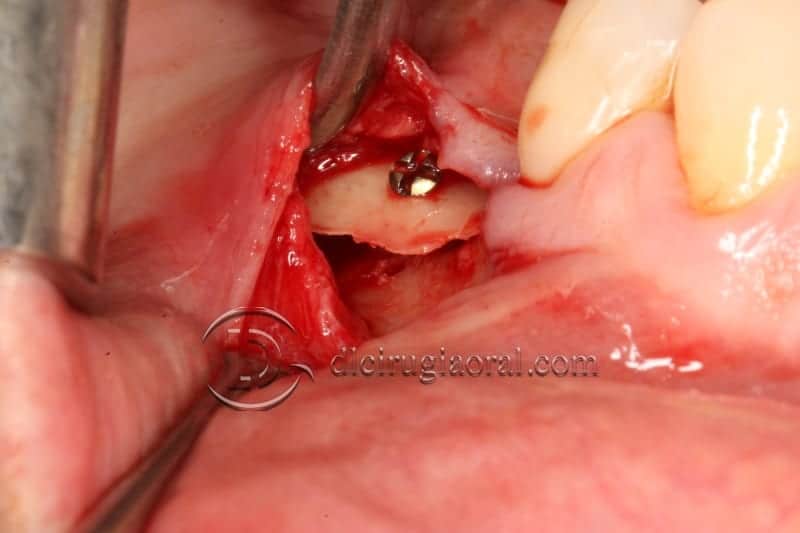

#1. The Tunnel Approach Technique

When accessing the area that has to be reconstructed through a subperiosteal tunnel, and performing the whole procedure through the tunnel approach will give us two significant advantages:

1. No incisions are made over the crest, so no suture will be there, reducing to zero the possibility of wound dehiscence

2. As far as no incisions are made over the periosteum that is covering the graft, its osteogenic and revascularization capacity remains intact.